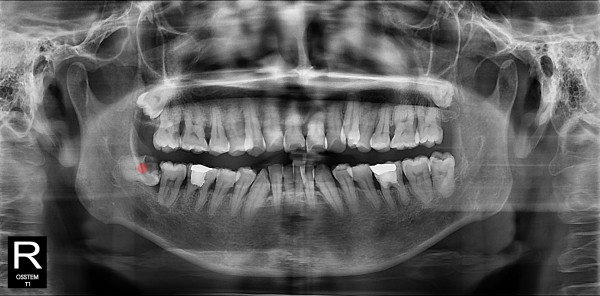

사랑니발치 30대/여성

ae27575af29d49719312fde5a1f0cca6_1764402230_7515.jpg